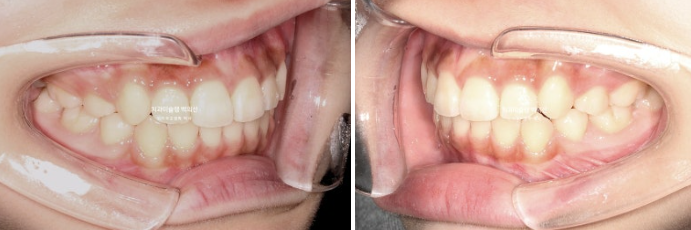

24.11

치료시작 1년 1개월차 모습입니다.

51번 장치를 끼고 있던 시기입니다.

발치공간은 1/3가량 남아있으며 덧니는 해소가 되었습니다.

배열은 많이 좋아졌지만 일부 장치가 안 맞는 부분이 있어 일찍이 재제작에 들어갔습니다.

남은 52~88개 장치는 아깝지만 폐기하게 됩니다.

한달간의 장치 재제작을 기다려 24년 12월부터 두번째세트 장치를 끼기 시작합니다. 두번째 세트 장치는 16개가 나왔습니다.